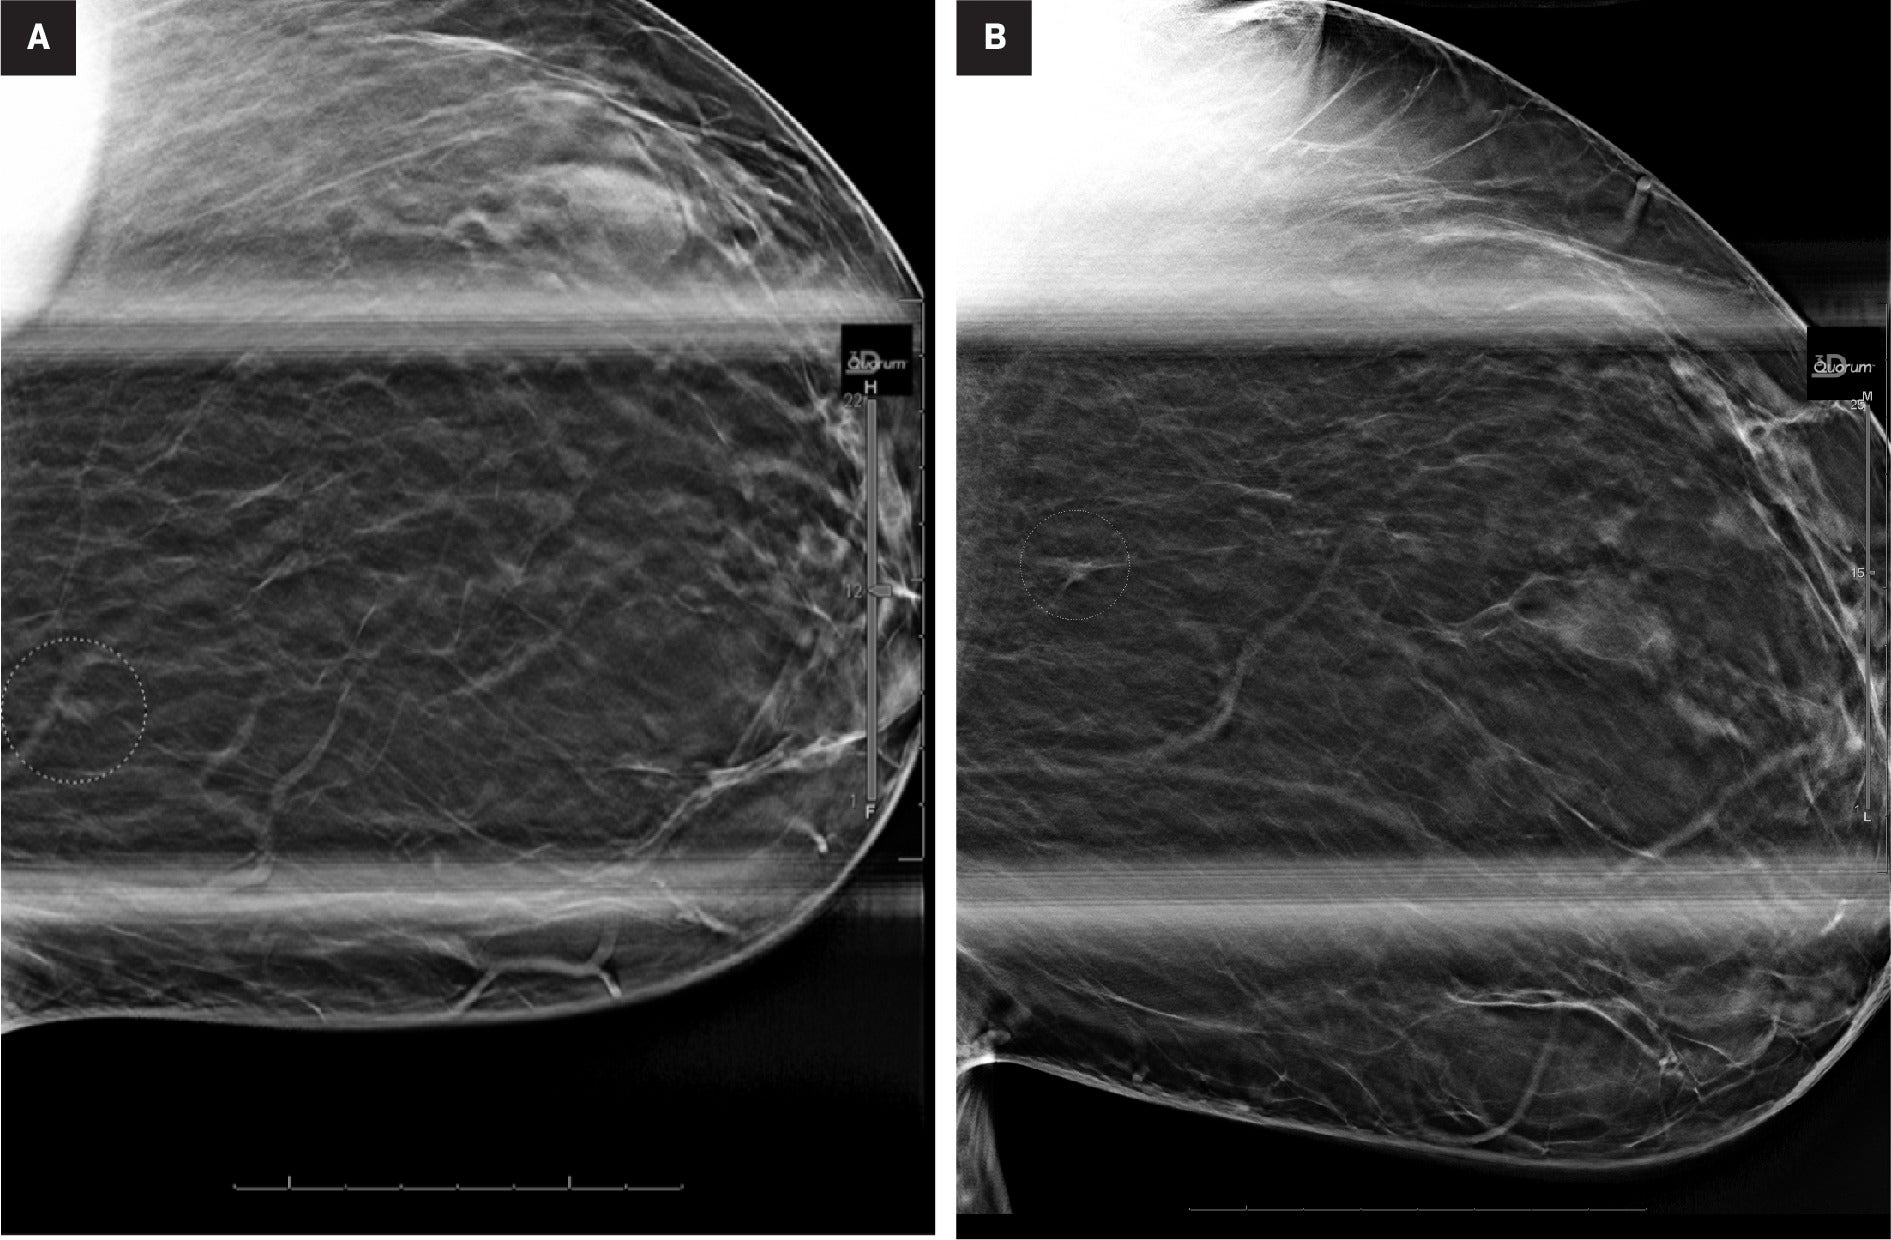

The patient was called back for diagnostic CC and MLO spot compression mammographic views with DBT, which confirmed the presence of a 0.6-cm focal asymmetry in the upper, inner left breast, posterior depth. ( Figure 2 )

Diagnostic spot compression views with DBT in the CC (A) and MLO (B) projections confirm a focal asymmetry in the upper inner left breast, posterior depth (circles)